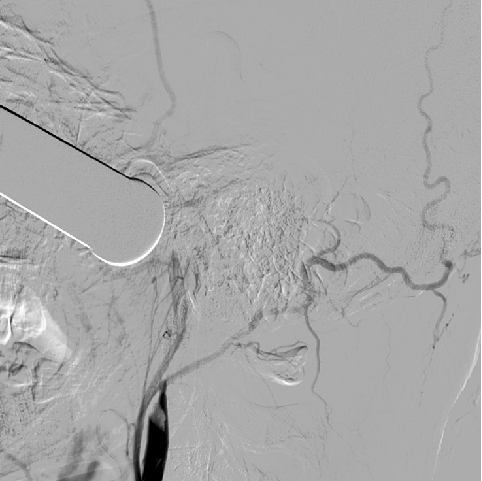

2014-9-29 DSA

介入手术:(缺Fagarty /Merci/ Penumbra球囊导管、带膜支架)颈内动脉颅内外段置球囊保护,拔异物。